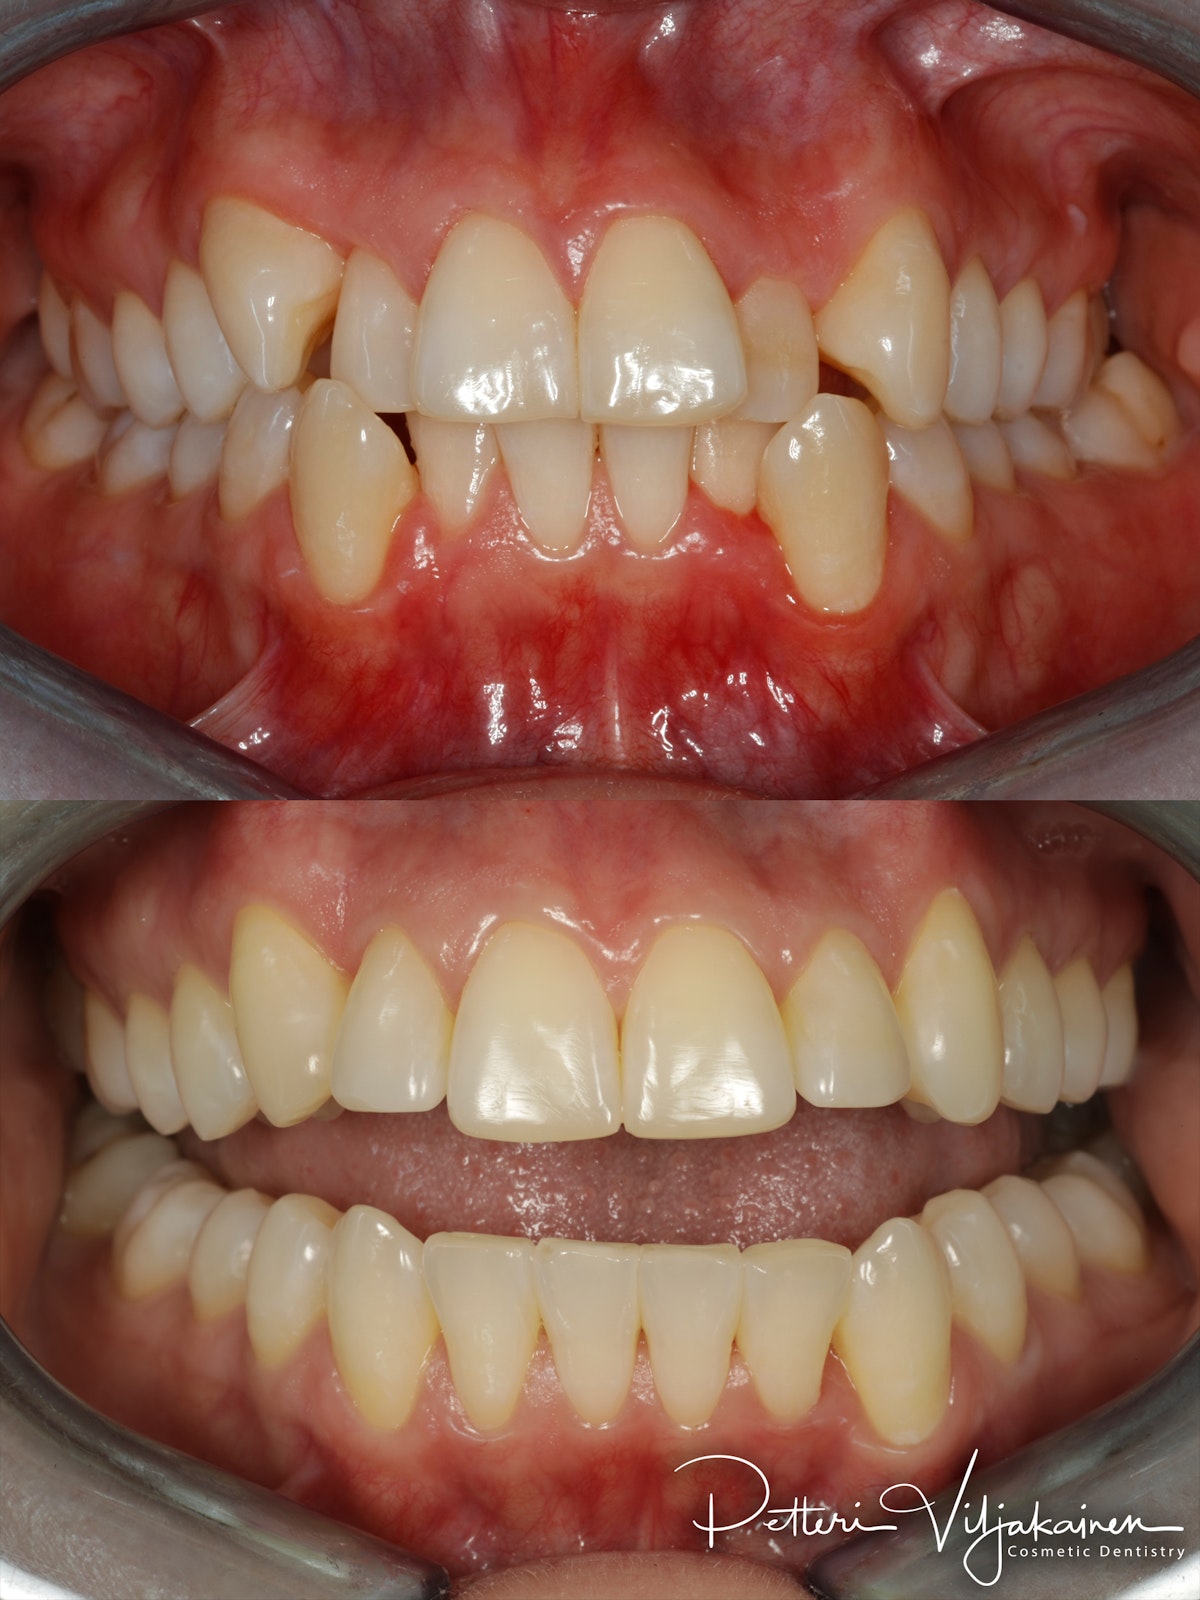

10kk hoito (Comprehensive). Etuhampaiden kärkien viimeistely kerrostusmuoveilla.